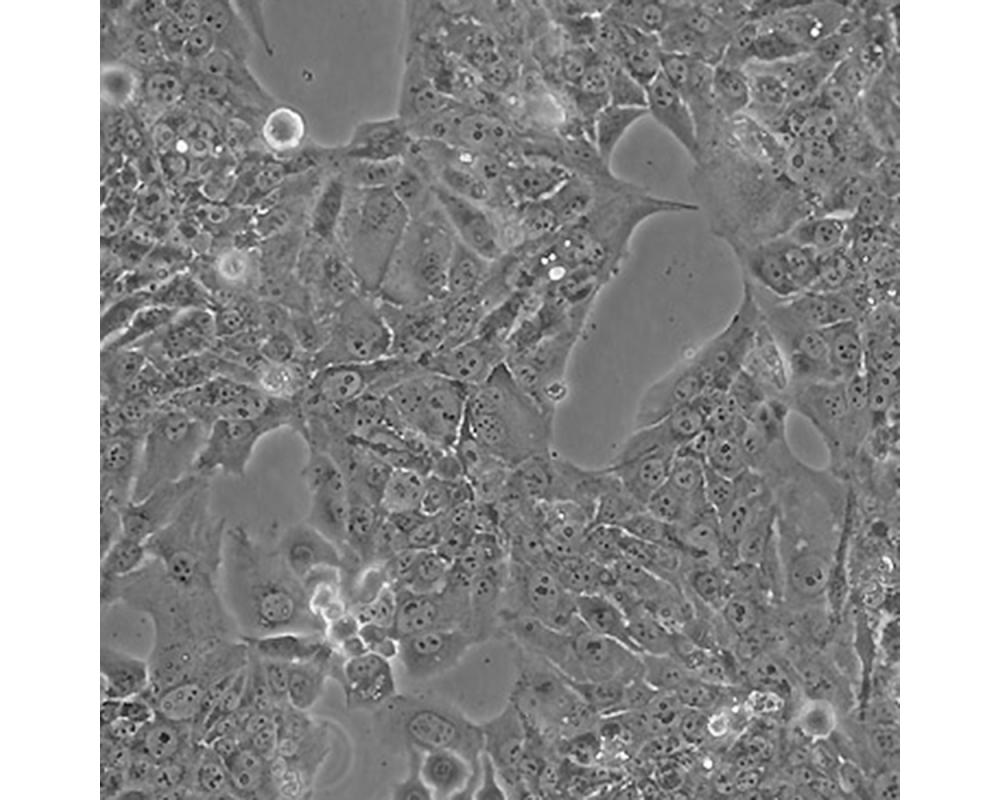

BeWo

中文名稱 人胎盤絨膜癌細(xì)胞

組織來源 妊娠性絨癌

形態(tài)特征 上皮樣

生長(zhǎng)特性 貼壁生長(zhǎng)

特征特性 取自人絨癌腦轉(zhuǎn)移組織,在倉鼠頰囊移植傳代8年。利用移植瘤組織進(jìn)行體外培養(yǎng),建立細(xì)胞系。利用不同傳代方法建立了不同亞系,JEG-3是其衍生克隆。該細(xì)胞可以產(chǎn)生雌激素、孕激素、雌酮、雌二醇、雌三醇、hCG、胎盤催乳素、角蛋白。